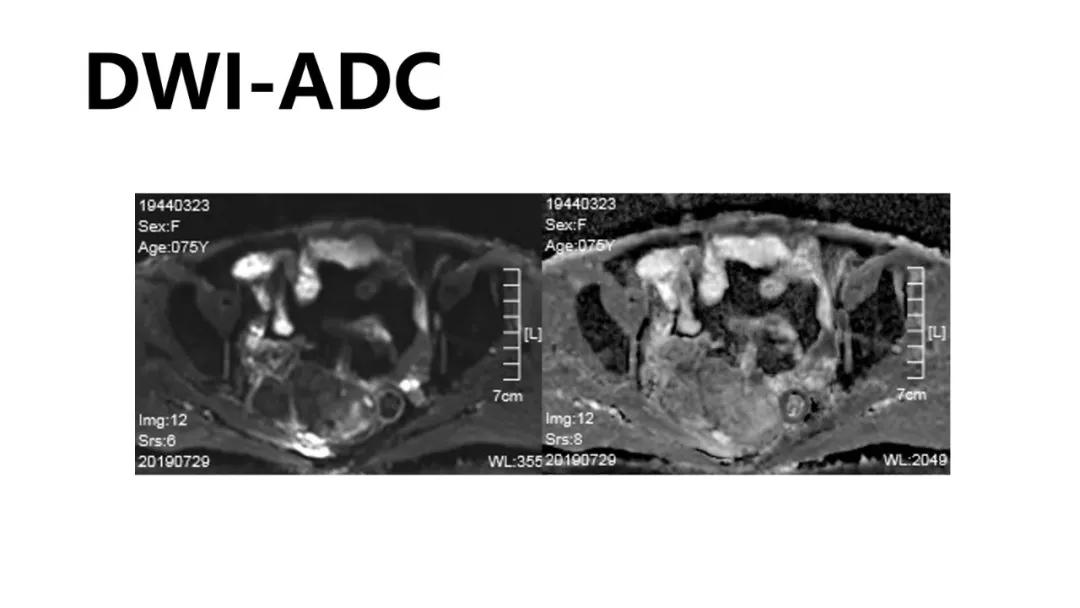

病理:浆液性囊腺癌

病理:颗粒细胞瘤